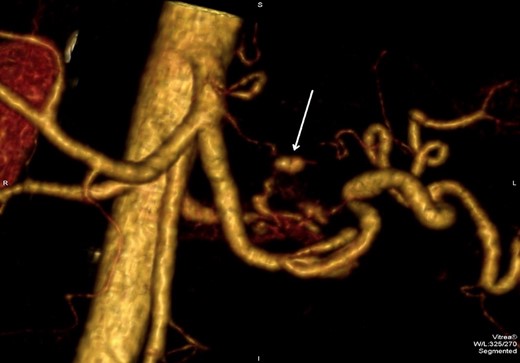

However, 4 days after the ultrasound guided injection, the patient collapsed on the ward with haematemesis and hypovolaemic shock. He was resuscitated initially with intravenous fluids and transfusion of blood products and remained alert with no abdominal signs. An emergency gastroscopy showed a 1.5 cm gastric ulcer on the posterior gastric wall with a large clot in the upper stomach but no active bleeding. A repeat CT abdomen demonstrated persistent flow in the pseudoaneurysm (Fig. 4).

CT abdomen image post thrombin injection shows flow in the pseudoaneurysm (arrow).